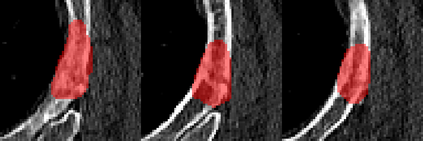

Rib fractures are a common and potentially severe injury that can be challenging and labor-intensive to detect in CT scans. While there have been efforts to address this field, the lack of large-scale annotated datasets and evaluation benchmarks has hindered the development and validation of deep learning algorithms. To address this issue, the RibFrac Challenge was introduced, providing a benchmark dataset of over 5,000 rib fractures from 660 CT scans, with voxel-level instance mask annotations and diagnosis labels for four clinical categories (buckle, nondisplaced, displaced, or segmental). The challenge includes two tracks: a detection (instance segmentation) track evaluated by an FROC-style metric and a classification track evaluated by an F1-style metric. During the MICCAI 2020 challenge period, 243 results were evaluated, and seven teams were invited to participate in the challenge summary. The analysis revealed that several top rib fracture detection solutions achieved performance comparable or even better than human experts. Nevertheless, the current rib fracture classification solutions are hardly clinically applicable, which can be an interesting area in the future. As an active benchmark and research resource, the data and online evaluation of the RibFrac Challenge are available at the challenge website. As an independent contribution, we have also extended our previous internal baseline by incorporating recent advancements in large-scale pretrained networks and point-based rib segmentation techniques. The resulting FracNet+ demonstrates competitive performance in rib fracture detection, which lays a foundation for further research and development in AI-assisted rib fracture detection and diagnosis.